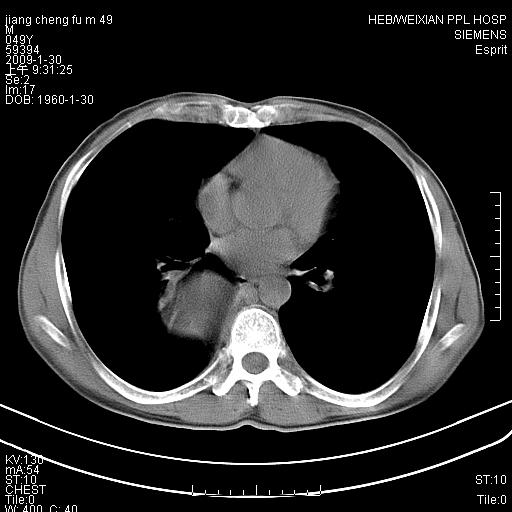

男性,49岁,主因胸痛,右肺呼吸音低。胸片提示肺占位

考虑右侧脊柱旁沟囊性病变。1:支气管囊肿或食管囊;2:神经源性肿瘤。

右后纵隔囊性占位;考虑为:1)淋巴管囊肿。2)食管囊肿。建议:进一步检查。

在分析这个病变时,首先病灶边界清晰,但其内密度不均匀,有条索状状实性成分,肿块的外侧壁亦呈一不均匀的厚壁改变,因此支气管囊肿的可能性不大。主要考虑神经源性肿瘤(主要考虑神经鞘瘤,因为它囊变的机率比较高),其次考虑肺膈离征,行增强扫描如发现来自胸主动脉供血动脉血管可确诊。

考虑右侧脊柱旁沟囊性病变,囊骨有分隔,囊壁较厚。1:神经源性肿瘤;2:食管囊肿或淋巴管囊肿。支持!

囊状肿块内有线样软组织分隔,支气管囊肿及食管囊肿可不考虑。我考虑:1、囊性肺膈离征(需要增强扫描来排除)。2、神经鞘瘤。3、淋巴管囊肿。

可惜了,仍然是不知道最后的结果,依照楼主所说家属的反映,‘良性病变,完全切除’,还是考虑神经纤维瘤可能性大一些